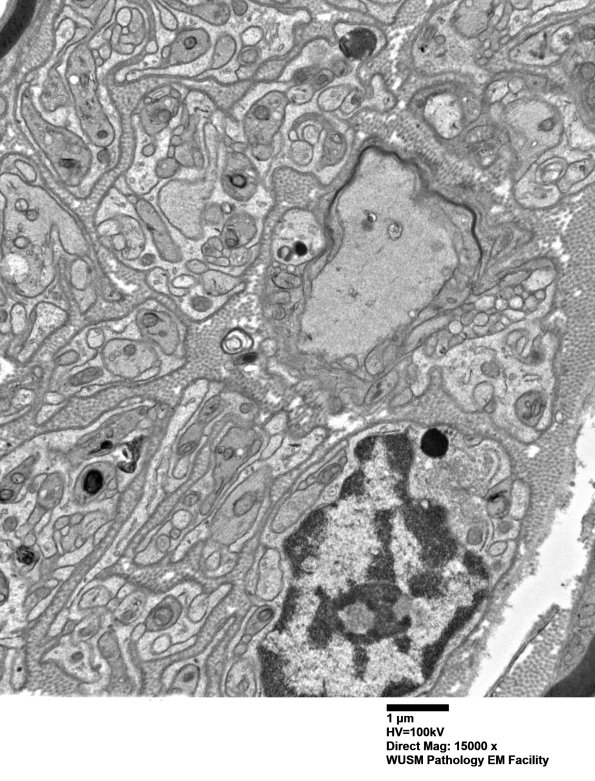

Washington University Experience | PERIPHERAL NEUROPATHY | 1 NORMAL NERVE ANATOMY | 6 Infant Peripheral Nerve | 2B5 W20-132 A (Case 2) tibial_006 - Copy

2B5 W20-132 A (Case 2) tibial_006 - Copy

A higher magnification image of #2B4. (electron micrograph)